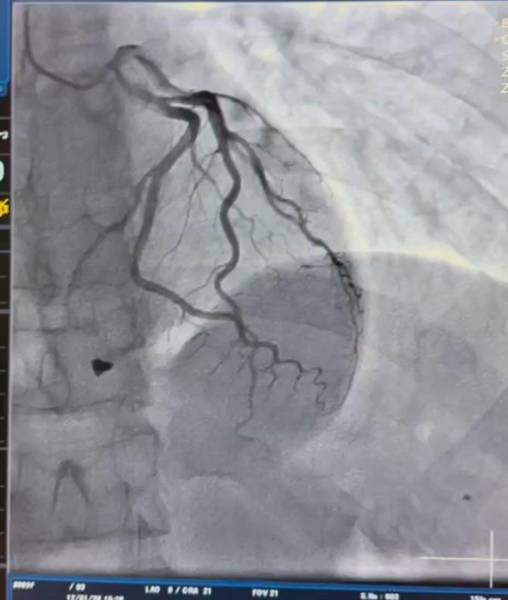

"Під час ретельного обстеження пацієнта встановлено: металевий уламок локалізувався в зоні клапанного апарату серця з пошкодженням папілярного мʼяза тристулкового клапана. Це не просто травма, а загроза втрати повноцінної та компетентної роботи клапана серця. Після детального аналізу анатомії травми кардіохірургічною командою лікарні виконано видалення вогнепального осколка та пластику тристулкового клапана, що дозволило відновити його функцію і забезпечити стабільну роботу серця", – йдеться у повідомленні.